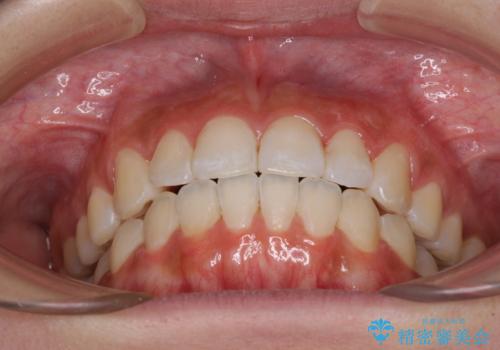

前歯のデコボコが気になる インビザラインによる矯正治療

- 上下前歯のデコボコを気にして来院された患者様です。

インビザラインによる上下歯列の拡大と、IPR(歯と歯の間を削る)にるスペースの獲得により、前歯のデコボコを改善することとしました。

しっかりと装着時間を遵守してくださったので、思い通りの歯列に整えることができました。

結婚式前に終了させることができ、患者様には大変満足していただきました。